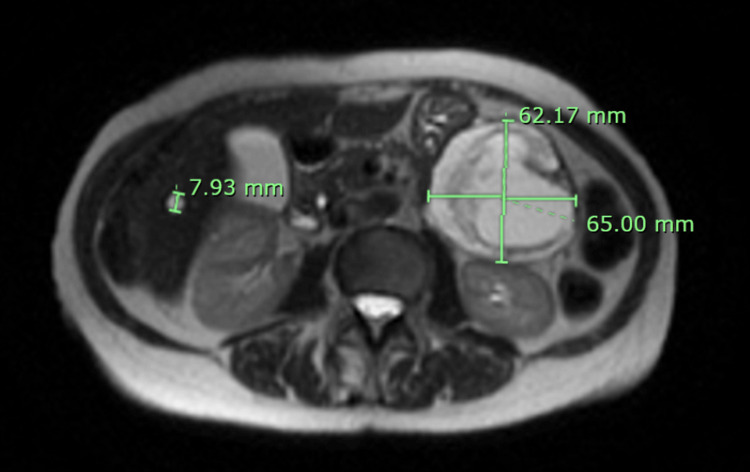

入院检查结果:体格检查无腹部压痛及其他阳性体征。实验室检查除碱性磷酸酶轻度升高(145 IU/L)外均正常。腹部及盆腔CT提示左腹部可见一约62×62×71 mm起源不明占位。腹痛自行缓解后未再发。腹部MRI进一步提示胰尾部大小约65.00×62.17×68.64 mm混合囊实性占位,呈周边强化并伴扩散受限(图1和图2)。该肿块可能起源于胰尾,考虑恶性可能,未见转移征象。

图1. MRI轴位SS-FSE序列图像。

腹部无对比剂MRI显示胰尾部复杂混合囊实性占位,伴周边强化及扩散受限,可能起源于胰尾,考虑恶性可能,未见转移征象